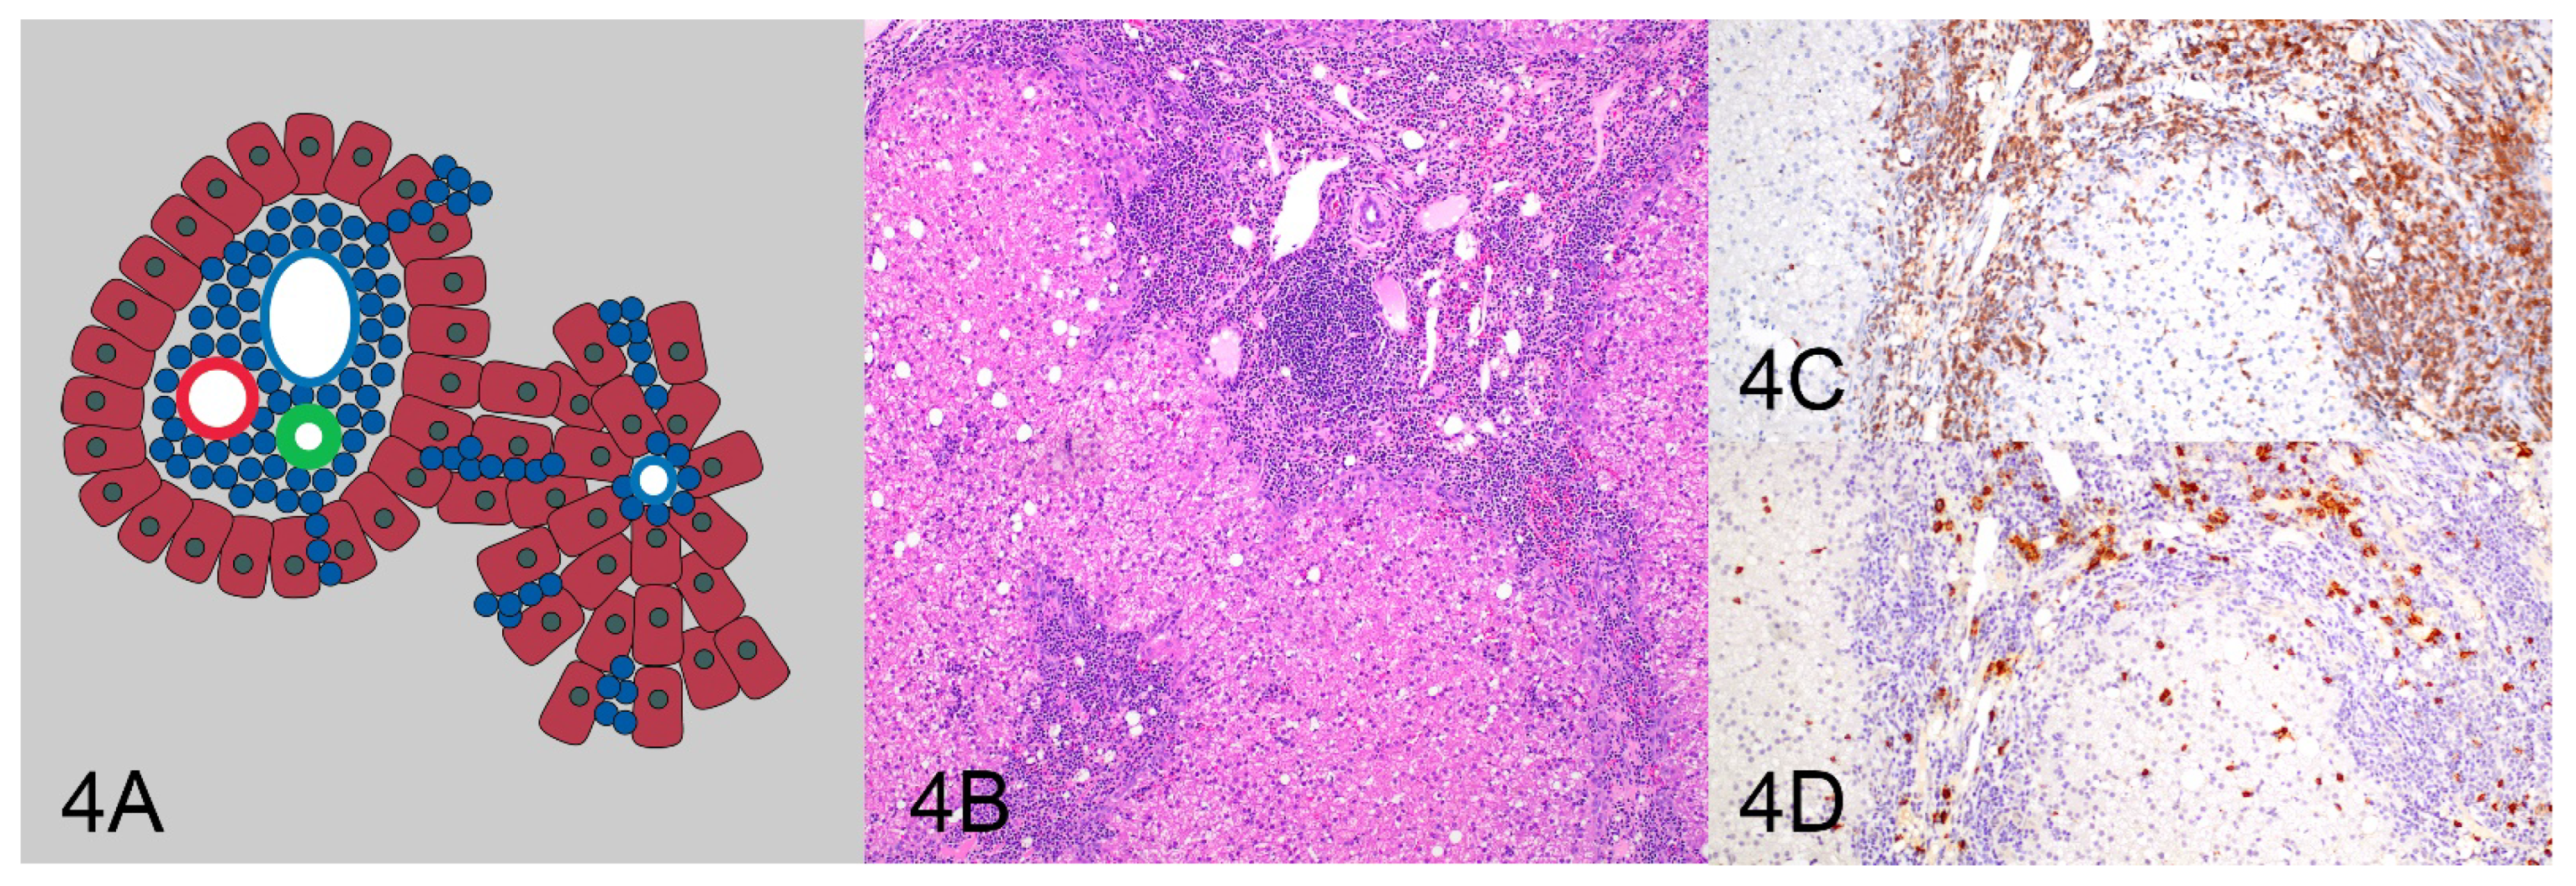

| Pattern 4: Periportal with sinusoidal extension | 8 (38.1%) | 13 (61.9%) | 21 (100%) |